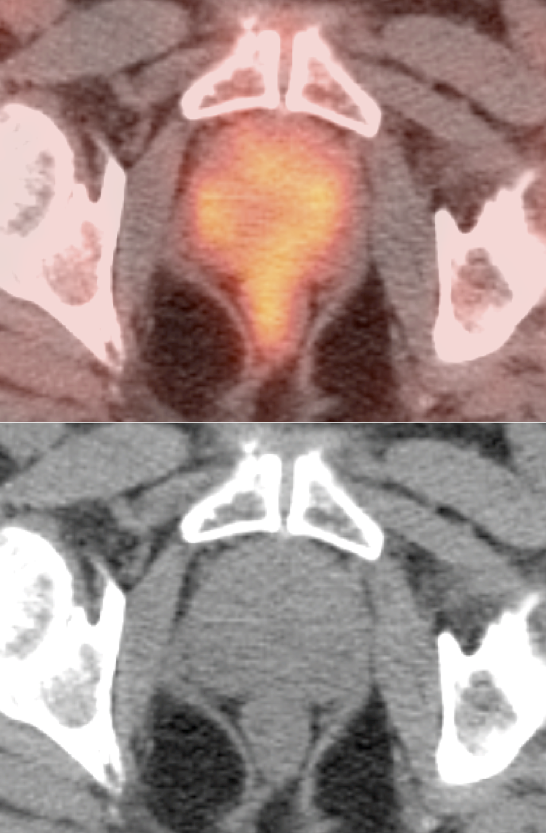

Normal Prostatic Uptake:

- The normal prostate typically demonstrates little or no FDG uptake.

- Mild diffuse prostate uptake is considered normal.

- Moderate or intense diffuse uptake typically reflects prostatitis.

- Although even focal FDG uptake in the prostate is often normal, correlation with PSA levels is advised, especially if the uptake is located in the peripheral zone (location of 70% of prostate cancers).

- Uptake centrally in the gland typically represents normal hypermetabolic urine in the prostatic urethra.

- Due to the poor FDG avidity of many prostate cancers, the overlap of increased uptake often associated with prostatitis, the marginal sensitivity of detecting pelvic nodal disease and the limitations created by superimposition of intense bladder activity, PET/CT currently has no role in the screening or diagnosis of prostate cancer. For similar reasons, it is generally of limited utility for initial staging of the disease.